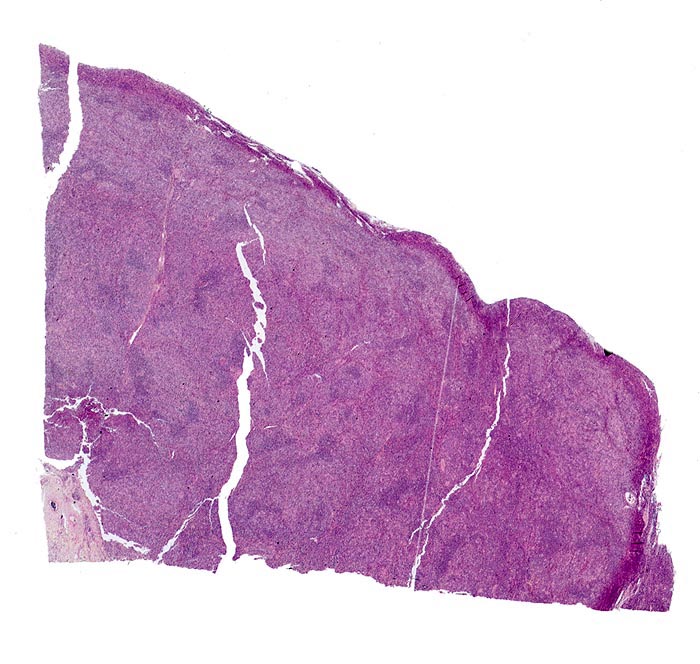

PathoPic – image database / PathoPic ID 3884 - Hodgkin-Lymphom, Mischzelltyp

Hodgkin-Lymphom, Mischzelltyp

Lymphknoten, Kopf-cervikal

Vollständige Aufhebung der normalen Lymphknotenstruktur. Lymphfollikel sind nicht vorhanden.

Vergrösserte zervikale und axilläre Lymphknoten, Fieber und Nachtschweiss.

Histologie

Scan